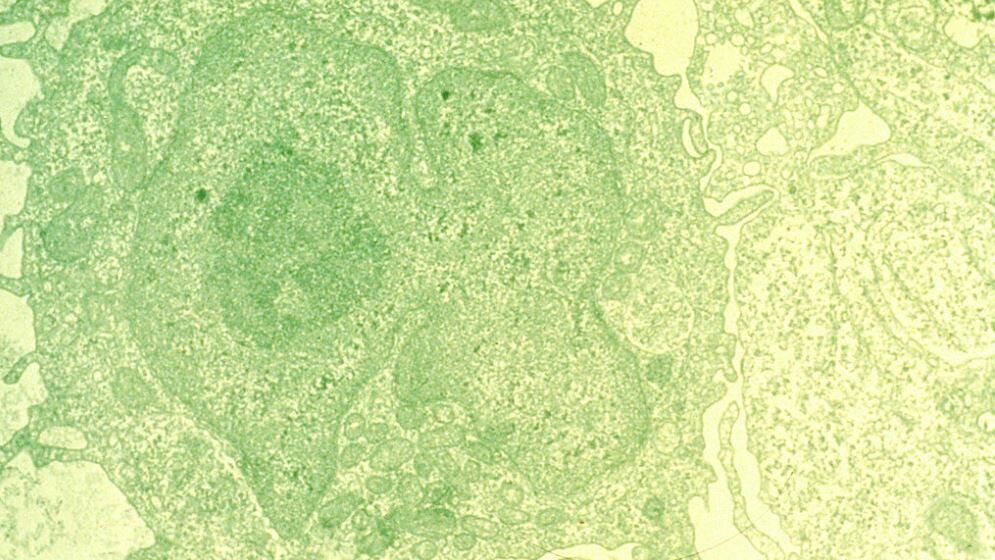

Etwa acht Prozent aller soliden Tumoren zeigen Veränderungen im Erbgut des BRAF-Gens, die als therapeutische Zielstruktur genutzt werden können. Die Mutation des B-Raf-Proteins an der Aminosäureposition 600 aktiviert einen Signalweg besonders stark, der am Wachstum und Überleben von Zellen beteiligt ist. Dies kann in Kombination mit weiteren Mutationen zu unkontrolliertem Zellwachstum und somit der Entstehung von Krebs führen. Fast 50 Prozent aller fortgeschrittenen Melanome, dem schwarzen Hautkrebs, besitzen eine Mutation im BRAF-Gen. Bei diesen Patienten setzen Ärzte den spezifischen BRAF-Hemmer Vemurafenib bereits ein. Bei der Haarzell-Leukämie (HCL) – ihr Name leitet sich von dem charakteristischen Aussehen der Zellausläufer der Krebszellen ab – liegen bei 95-100 Prozent aller Erkrankten ebenfalls Mutationen des BRAF-Gens vor. Auch hier wird Vemurafenib als zielgerichtete Therapie gegen das fehlerhaft aktivierte B-Raf-Protein als Behandlungsoption verwendet.